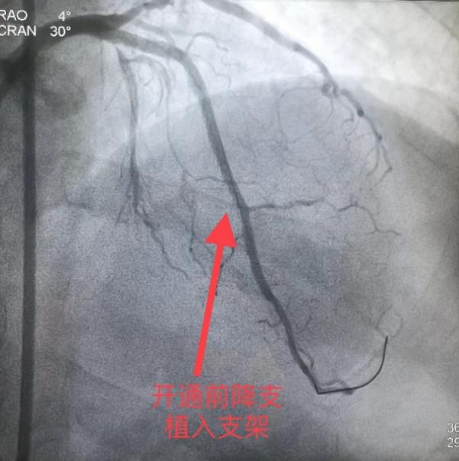

入院后立即完善术前检查和评估,第三天雷新军教授即带领景林德博士和李瑞峰住院医生为患者实施了手术,术中CAG显示:前降支7段和回旋支13段为CTO,因多次手术失败的原因,前降支7段存在明显的夹层和血肿病变,极大地增加了手术难度(图5)。经过缜密分析,雷新军教授决定首先尝试正向开通前降支CTO,若手术顺利再正向开通回旋支CTO,择期干预右冠脉。在不同体位造影指导下,雷新军教授仔细操控多种CTO导丝,历经约2小时终于成功开通了前降支和回旋支CTO,休息数天后又成功干预了右冠脉,手术效果良好(图6)。

图5 青海省人民医院造影资料

图6 青海省人民医院PCI术后资料